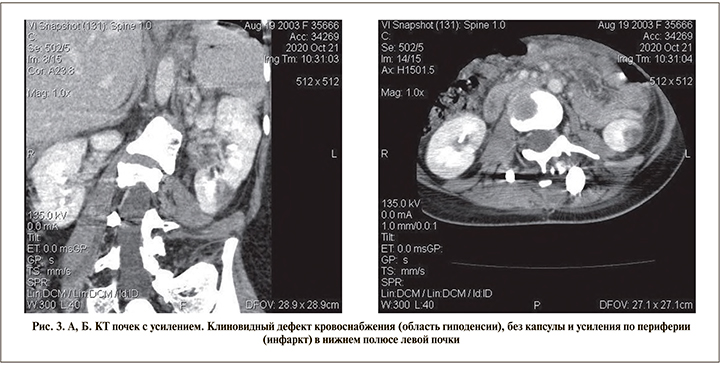

После получения отрицательных анализов ПЦР на COVID-19 20.10.2020 пациентка переведена в ГУ РДКБ для дальнейшего лечения. При переводе отмечается течение септического процесса с положительной динамикой по течению кардиопатии, кардита, поражения легких. Состояния почек по данным УЗИ: размер левой почки – 116×45×44 мм, правой – 103×43×45 мм, чашечно-лоханочная система (ЧЛС) не расширена. Отмечается некоторое увеличение размеров левой почки с однородным гипоэхогенным участком паренхимы клиновидной формы в нижнем полюсе левой почки, не имеющим капсулы. Контур почки не деформирован в проекции образования, дыхательная подвижность почки сохранена, прилежащая паранефральная клетчатка без структурных изменений. При допплеровском сканировании в нижнем полюсе левой почки выявлено аваскулярное образование (рис. 1).